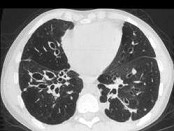

- 单项选择题男,18岁, 咳嗽,咳痰, 咯血半月余,CT检查如图, 最可能的诊断是 ( )

A、过敏性肺炎

B、支气管扩张

C、原发性肺结核

D、大叶性肺炎

E、肺癌